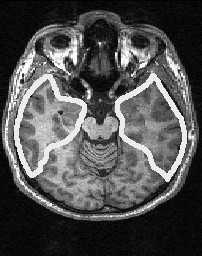

МРТ головного мозга. Аксиальный срез на уровне ножек мозга. Границы височной доли.